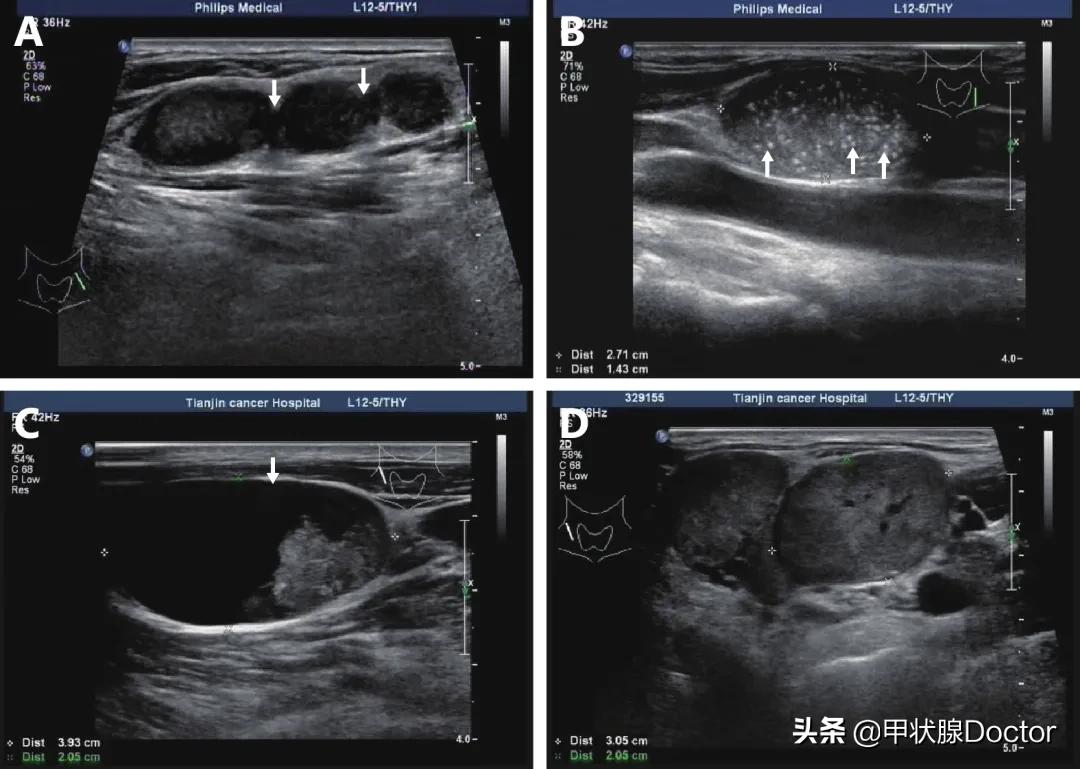

超声是甲状腺结节影像学检查的首选方法,根据以下特征可判断淋巴结的良恶性:

1、大小。 单纯淋巴结增大不是恶性特征,但如果复查持续增大,强烈提示为转移性淋巴结。

2、形态。 正常淋巴结一般呈长椭圆型,恶性者变为近圆形,长短径比值小于2(L/T<2)。

3、微钙化(≤1mm钙化灶)。 甲状腺乳头状癌淋巴结转移钙化率高。

4、皮质内高回声: 甲状腺球蛋白的沉积常表现为高回声,是甲状腺乳头状癌的特征性表现。

5、皮质内无回声: 超声中显示为无回声或回声透亮区(囊性坏死),提示肿瘤细胞的浸润导致液化性坏死。

6、周边型血流信号。 为恶性淋巴结外周皮质异常增生,提示意义较强。正常淋巴结为门样血流或乏血流。

7、边缘锐利。 恶性淋巴结边界不清提示被膜外浸润。

8、周边软组织水肿及淋巴结融合成团通常是结核性的。

总结:圆、钙、回声高或无、周边血流提示恶性倾向,复查短期增大也可疑!